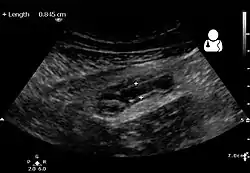

Ultrasound

Abdominal ultrasonography, preferably with doppler sonography, is useful to detect appendicitis, especially in children. Ultrasound can show the free fluid collection in the right iliac fossa, along with a visible appendix with increased blood flow when using color Doppler, and noncompressibility of the appendix, as it is essentially walled-off abscess. Other secondary sonographic signs of acute appendicitis include the presence of echogenic mesenteric fat surrounding the appendix and the acoustic shadowing of an appendicolith.[45] In some cases (approximately 5%),[46] ultrasonography of the iliac fossa does not reveal any abnormalities despite the presence of appendicitis. This false-negative finding is especially true of early appendicitis before the appendix has become significantly distended. Also, false-negative findings are more common in adults where larger amounts of fat and bowel gas make visualizing the appendix technically difficult. Despite these limitations, sonographic imaging with experienced hands can often distinguish between appendicitis and other diseases with similar symptoms. Some of these conditions include inflammation of lymph nodes near the appendix or pain originating from other pelvic organs such as the ovaries or Fallopian tubes. Ultrasounds may be either done by the radiology department or by the emergency physician.[47]